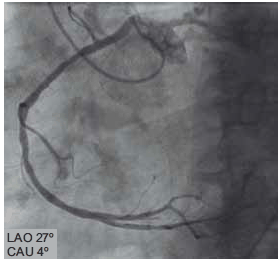

Ao realizar cineangiocoronariografia de mulher com 45 anos, tabagista, com queixa de dor torácica, observa-se o seguinte achado.

(Arquivo pessoal; imagem usada com autorização)

Trata-se de origem anômala